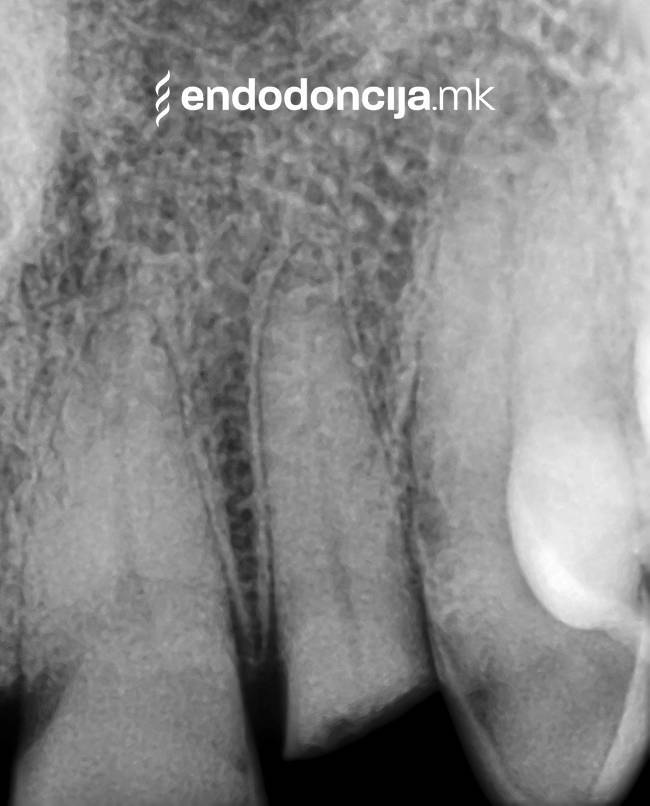

Με τη σωστή θεραπεία, όχι μόνο οι οξείες φλεγμονές αλλά και οι χρόνιες μπορούν επίσης να αντιμετωπιστούν με επιτυχία. Αυτά μπορεί να προκαλέσουν πόνο ή μερικές φορές ακόμη και εντελώς χωρίς συμπτώματα. Η έγκαιρη ανίχνευση και εξάλειψη τέτοιων φλεγμονών είναι ζωτικής σημασίας για τη μακροχρόνια συντήρηση των δοντιών.